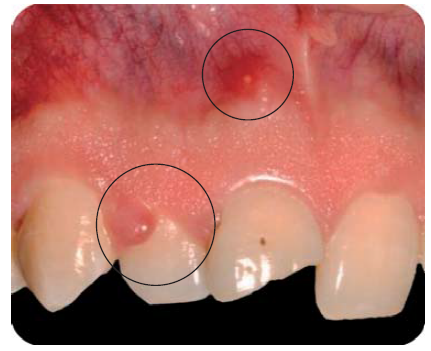

Paciente masculino de 21 años de edad, sano, presentando LDT al caer de una bicicleta; con fractura coronaria complicada de los dientes: 12, 11 y 21, con una evolución de 48 horas (Figura 1).

Debido a la evolución de dos días desde el accidente, el paciente presenta dolor e inflamación a la exploración extraoral, durante la exploración intraoral se observa la exposición pulpar de los dientes involucrados (Figura 2) e indica el tratamiento de urgencia a seguir, para disminuir el dolor e inflamación.

Durante la exploración intraoral, se observa una lesión fistulosa a nivel del ápice del diente 11 y el paciente refiere que los síntomas han disminuido con el transcurrir de los años (Figura 17).

Estos signos (Cuadro I) y síntomas, sumados con la imagen radiográfica confirma el daño pulpar del diente 11.

Fractura no complicada de corona del diente 11, presentando necrosis pulpar con periodontitis apical crónica supurativa; gingivitis inducida por placa dentobacteriana y agrandamiento gingival en el diente 12.